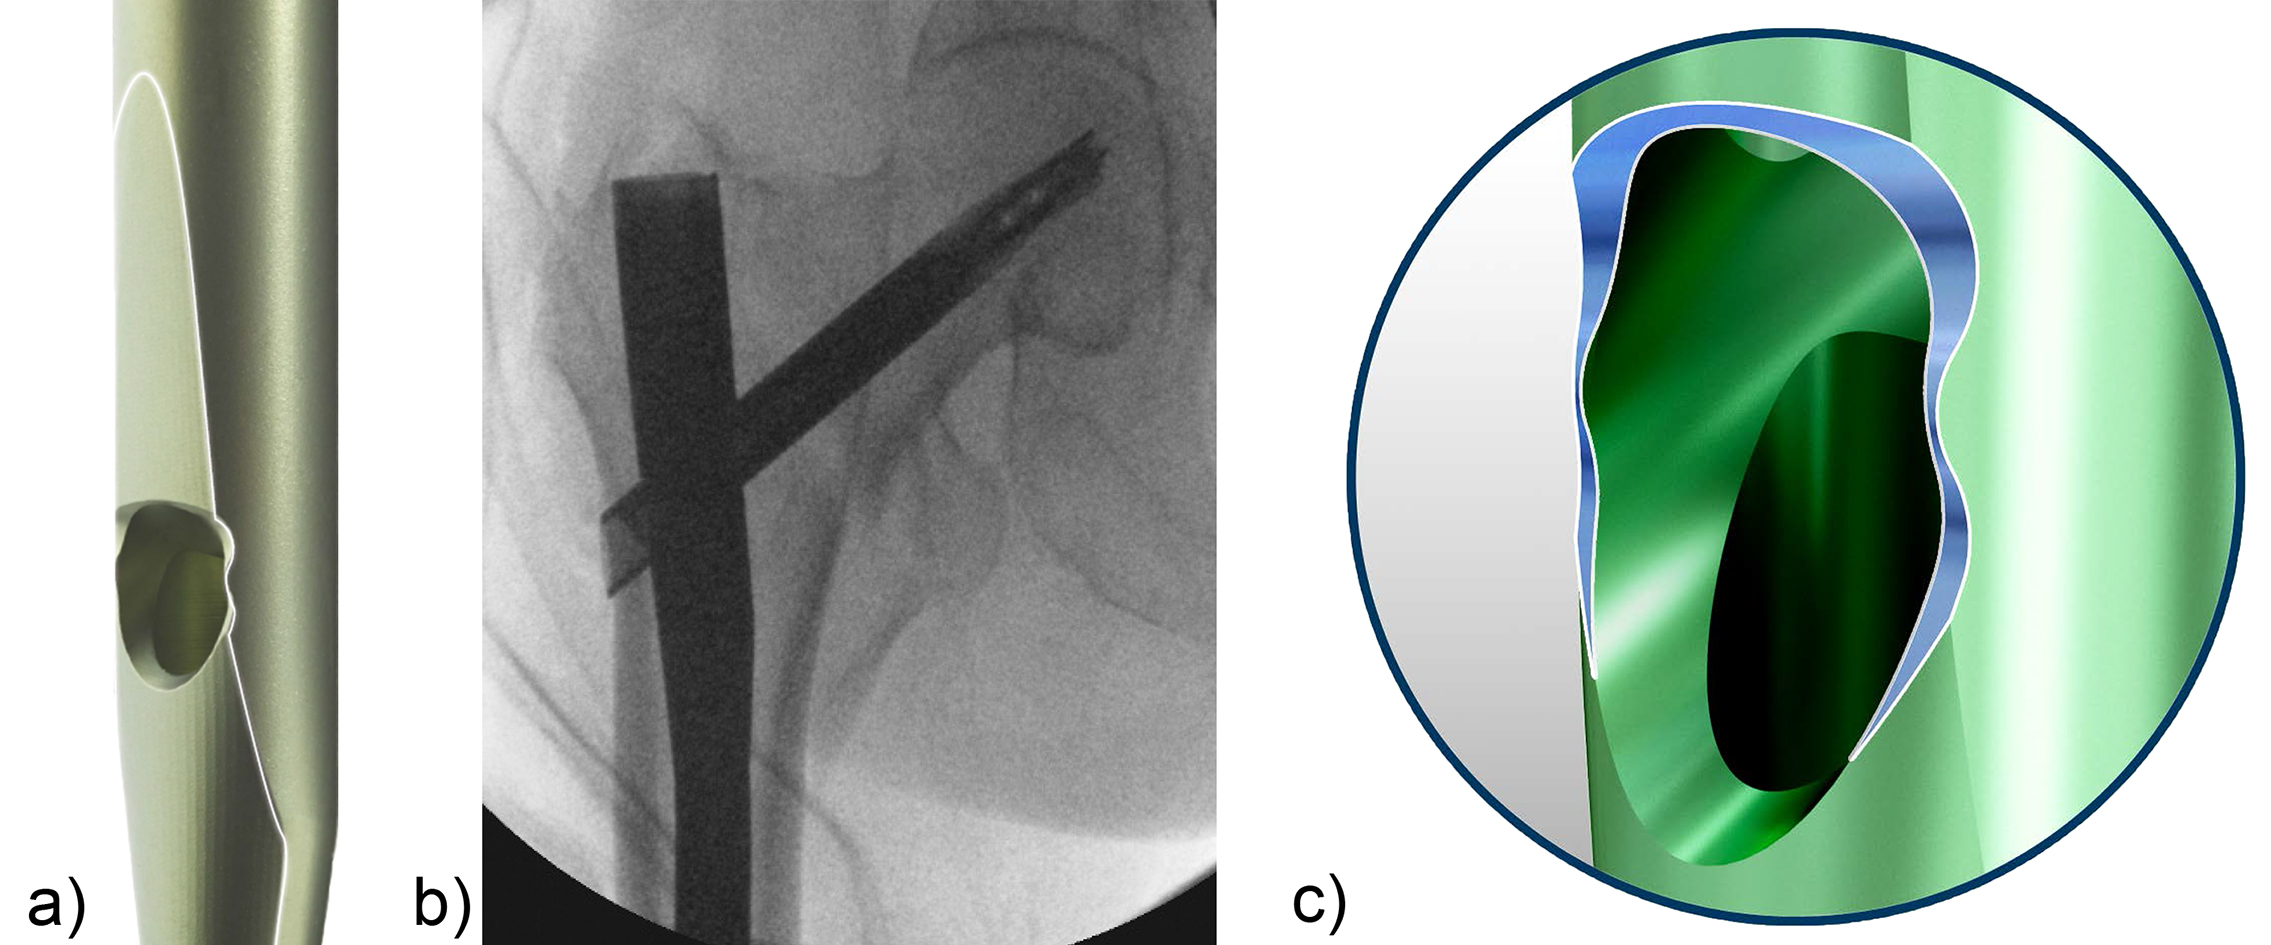

The combination of a large proximal nail diameter and a very lateral entry point has been identified as a potential reason for such a loss of reduction. As a result, a smaller diameter nail with a laterally flattened profile to more appropriately respect the anatomy of the proximal lateral femoral wall would be advantageous. Both design features have been realized with the new nail. The smaller 15.66 mm proximal nail diameter of the TFNA (compared to 16.5 mm and 17 mm for PFNA/PFNA-II and TFN) and the LATERAL RELIEF CUT design (Fig 4) of the proximal nail end serve to reduce the potential impingement of the nail with the lateral femoral wall and the HNF. Both of these issues could result in varus malalignment and a loss of reduction, which remain key indicators for an increased risk of cut-out. The small proximal nail diameter also helps to preserve bone in the insertion area, which is especially beneficial in the femora of small stature patients.

Evaluating nail fatigue is a key stage in the preclinical analysis of new implant designs. The median fatigue limit for the TFNA nail was 24% higher than that of the Gamma 3 nail and 47% higher than that of the InterTAN nail. This increase in fatigue strength is likely attributed to the use of a high-strength Ti-Mo (Ti-15Mo) alloy and the design features of the nail (Fig 4c).